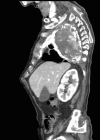

Empyema necessitans is a rare clinical finding nowadays. We report the case of a patient admitted in our ward for investigation of an unknown onset anterior chest wall mass, with no accompanying signs or symptoms. It is noteworthy that the patient had had pulmonary tuberculosis submitted to thoracoplasty more than 60 years before. Thoracic MRI showed a large heterogeneous mass, with a thick wall and internal septations located at the right anterior chest wall, as well as a heterogeneous content inside the right pleural cavity, with direct communication between both. An aspirative puncture of both masses was performed, with positive cultures for Mycobacterium tuberculosis, thus leading to the diagnosis of pleural tuberculosis with anterior chest wall empyema necessitans. A drain was inserted and antibiotics started. This case draws our attention to a very rare complication of pulmonary tuberculosis and its surgical treatment, though it aroused many decades after primary infection.